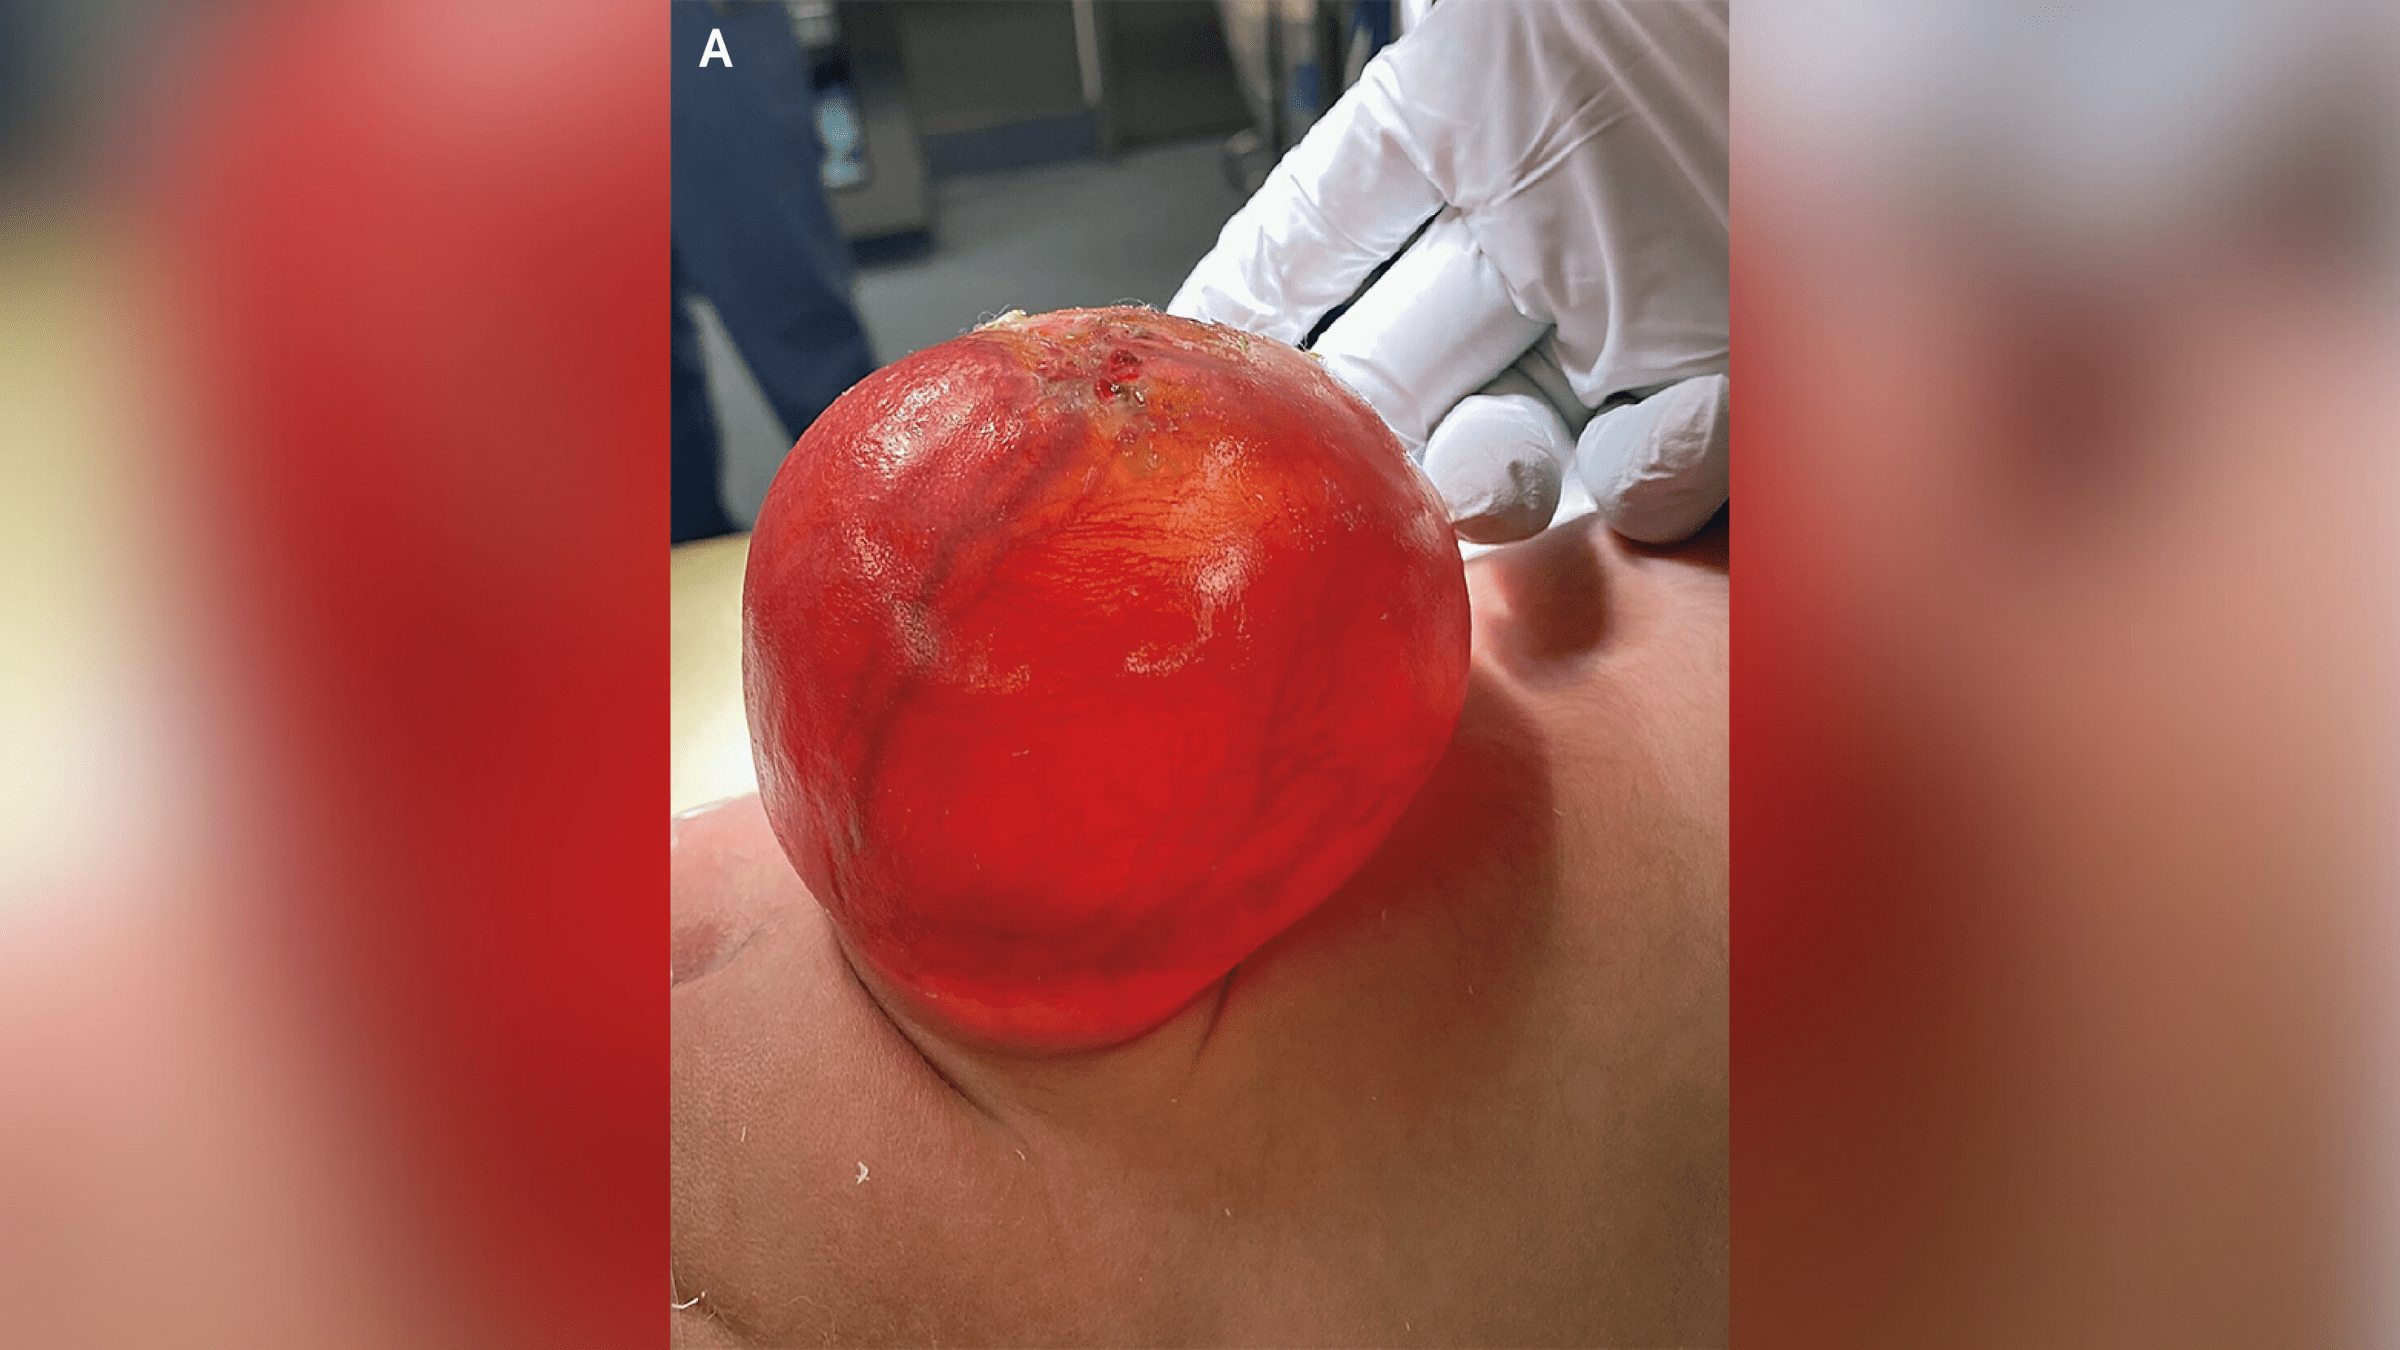

A vulgar nativity defect make a new-sprung baby to spring up a giant , crimson , balloon - like sac that pop from the lower back , a striking new image show .

The image was consume by doctor at Massachusetts General Hospital in Boston . The sac was around 3 inches ( 7.7 centimeters ) long , 2.8 inch ( 7.1 cm ) wide and 2.1 column inch ( 5.3 cm ) deep . It was cause by a neural tube defect — which , after nerve defects , is thesecond most common character of disability that is present from birth , affectingbetween 5 and 8 babies per 10,000 in the U.S.

now and again , though , tissue and fluid that embrace and protects the spinal cord is crowd through the interruption , create a sac - like , protruding body structure . This is what happened to the boy in the image , who had a specific version of spina bifida called meningocele .

The sac-like protrusion (pictured above) was caused by a condition known as meningocele.(Image credit: The New England Journal of Medicine ©2024)

In the boy ’s case , his parents choose for him to have OR to dispatch the sac and reconstruct his spinal cord after nascence . Four days after the surgery , he was discharge home , and at his six - calendar month checkup , Dr. said he was developing without any untoward effects .